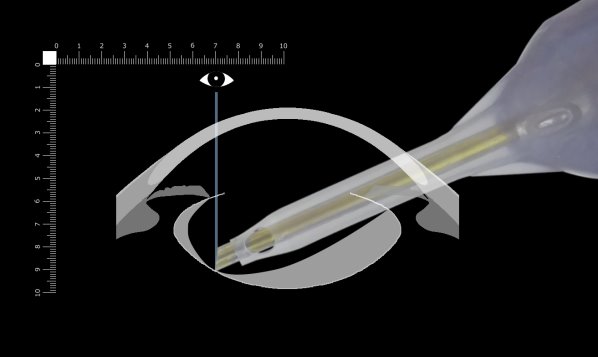

ここでは側面画像から考えます。

さらに先を見てみます。フェイコチップのベベルが垂直より手前(上)を向いている場所では掘っているところがよく見えます。チップの先端を見ながら掘っている限り大きく突き抜けることを回避できます。少し突き抜けたとしてもチン氏帯で固定されているため嚢がチップを閉塞することはありません。ここを深く掘るべきと考えます。